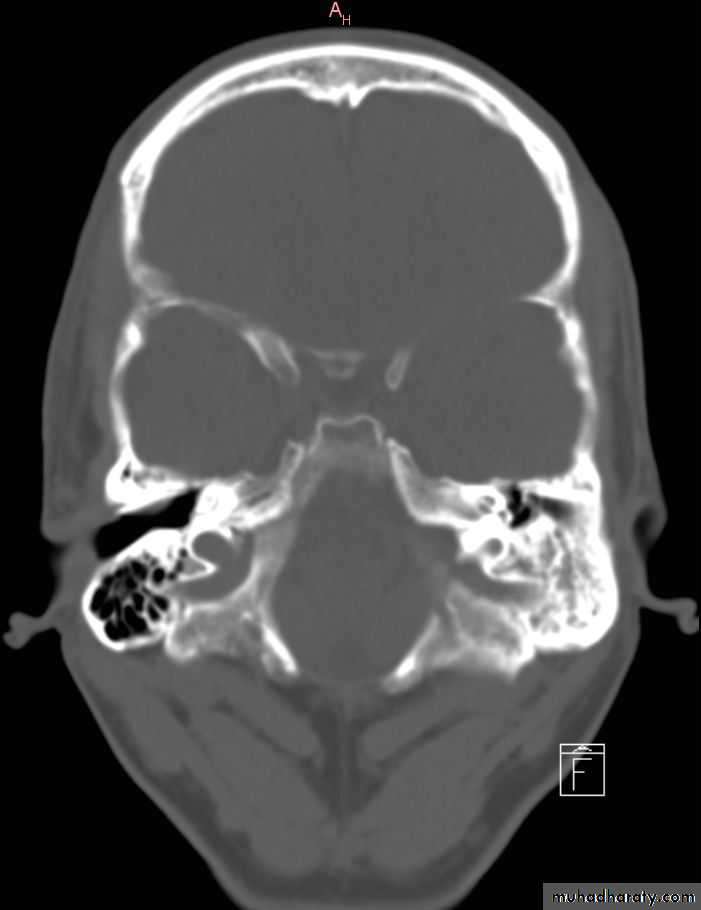

• Radiological findings reveals , sclerosis of the mastoid air cells

Expansion into the mastoid bone >>absorption of the bone(auto mastoidectomy)

• Radiological findings shows bone destruction in the advance stage